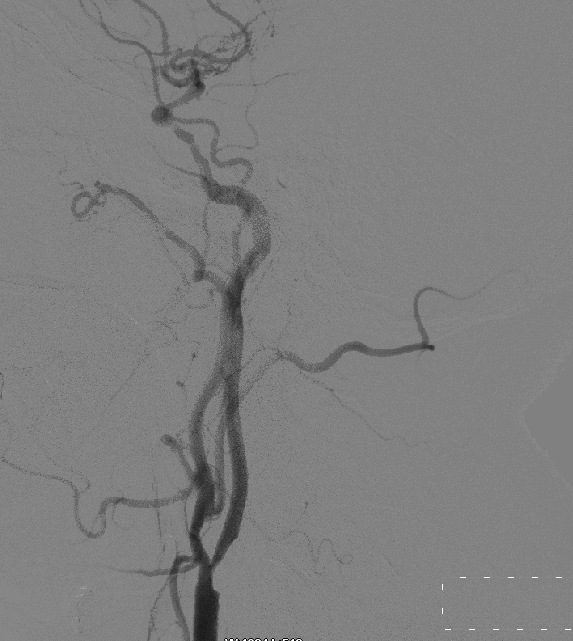

DSA :双侧颈动脉狭窄,冠脉三支病变

该患者中年男性,因“右侧肢体麻木无力10余年,加重伴头晕1年,一过性意识丧失一次”入院。入院后行DSA检查示双侧颈内动脉狭窄,手术指证明确,张勤奕教授于2011年11月25日成功为该患者施行右颈动脉内膜剥脱术,术后患者恢复良好。